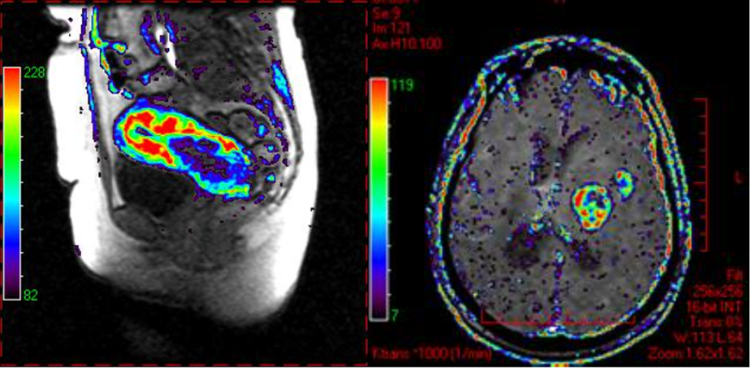

DCE-MRI permeability map color overlay on MRI in cervical cancer (left) and brain tumor (right). Data courtesy of Dr Nick Ferris, Peter MacCallum Cancer Center, Australia.